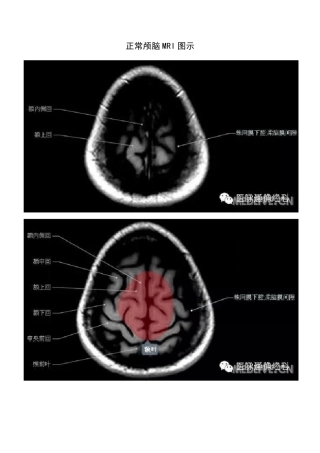

正常颅脑MRI 图示